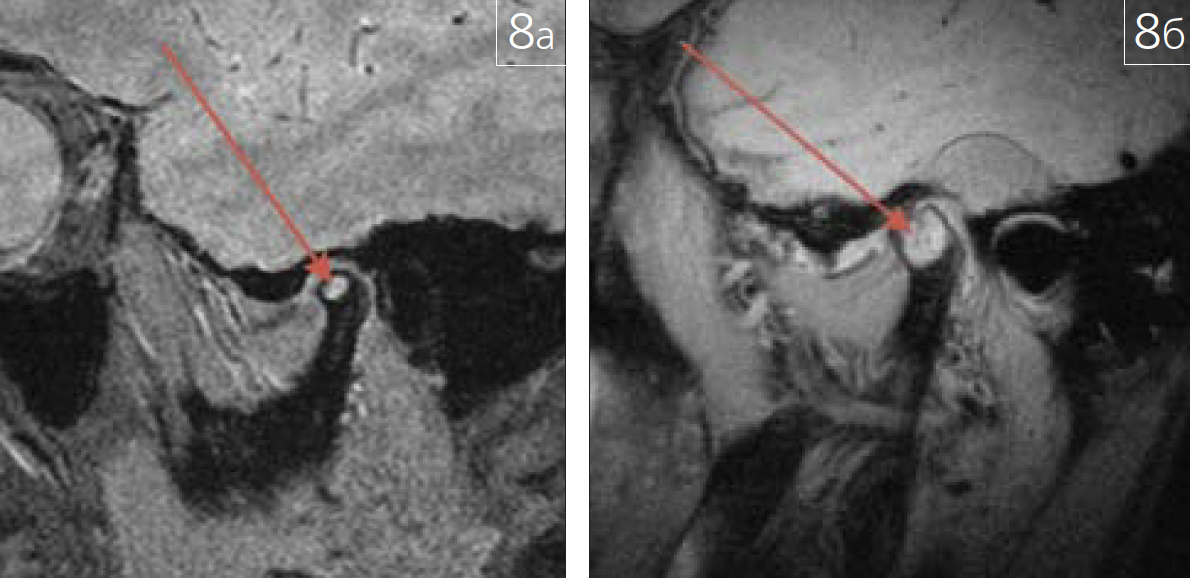

При помощи лучевых методов диагностики могут быть выявлены патологические изменения сочленяющихся поверхностей височно-нижнечелюстного сустава (ВНЧС). Примеры патологии костной ткани ВНЧС приведены на рис. 6 а, 6; 7 а, 6; 8 а, б.

Рис. 8. Случайные рентгенологическиенаходки при МР-диагностике дисфункции ВНЧС:а – интраоссальная киста головки мыщелкового отростканижней челюсти слева, сагиттальная плоскость, Т2*GREимпульсная последовательность в состоянии привычнойокклюзии;б – гигантоклеточная опухоль головки мыщелковогоотростка нижней челюсти справа, сагиттальная плоскость,PD импульсная последовательность с жироподавлениемв состоянии привычной окклюзии (зона патологическихизменений отмечена на рисунках красной стрелкой)